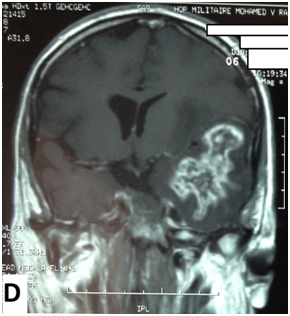

The cerebral MRI showed heterogeneous decreased signal intensity in T1, T2 and Flair-weighted images with variable sizes, surrounded by large area of increased signal intensity in T2 and Flair weighted-images with mass effect on the ipsilateral ventricle (Figure 1). The T1 sequences with intravenous gado injection showed heterogeneous gado enhancement corresponding to the area withT2 and Flair decreased signal intensity (Figure 2). This pattern corresponds to the “swiss cheese” and “soap bubble” aspect. The diffusion weited image showed increased ADC with increased water mobility in left temporal lobe (Figure 3). The radiological conclusion was temporal radionecrosis with large vasogenic edema, or the differential diagnosis of cerebral metastasis of the primary nasopharyngeal carcinoma. Thus, a spectroscopy was performed, and showed decreased peak of N-Acetyl-Aspartate (NAA) and Creatinine (Cr), with normal choline peak. The diagnosis of temporal radio necrosis was established. The patient was proposed to hyperbaric oxygen. His Oto-rhino-laryngeal examination was normal, as much s the chest X-ray. So a daily 45 minutes session, were performed for 10 successive days, associated to bolus of methylprednisolone (240mg/d for 10 days), anti-platelet agent (aspirin 160mg/d). The evolution was favorable, with regression of vestibular signs, improvement of memory and phasic troubles with recovering four lost points in MoCA score. The cerebral CT scan showed partial regression of the gliosis with no more mass effect on the ipsilateral ventricle (Figure 4).

Figure 1 Cerebral MRI in coronal T2-weighted image (A) and axial Flair-weighted image, showing heterogeneous decreasing signal intensity with variable sizes corresponding to necrosis area, surrounded by increased signal intensity corresponding to peri lesional edema with mass effect on the ipsilateral ventricle.